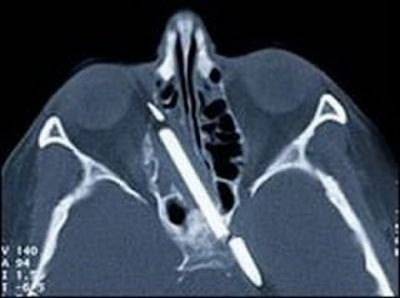

4. Pensil dalam kepala

Setelah menderita sakit kepala berat yang mengakibatkan terus mimisan selama 55 tahun, Margaret Wegner menjalani operasi pada bulan Agustus 2007. Saat inilah pensil sepanjang 3 inci akhirnya dikeluarkan dari kepalanya.

Uniknya, para dokter sebenarnya sudah mengetahui keberadaan pensil tersebut bersarang dalam kepala Wegner selama lima puluh tahun. Namun, selama itu pula dokter menunggu saat yang tepat. Dulu teknologi belum memungkinkan untuk operasi dan takut merusak kepala Wegner.

Untuk diketahui, Wegner mengalami kecelakaan saat berusuia 4 tahun dan menyebabkan sebatang pensil masuk ke dalam kepalanya.